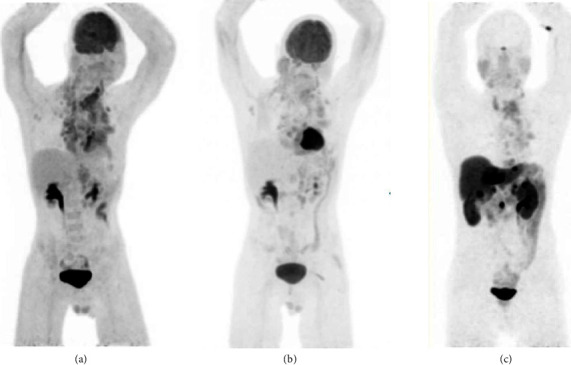

Thymic carcinoid tumours, especially in the context of multiple endocrine neoplasia type 1 (MEN 1), present significant clinical challenges due to their rarity and aggressive nature. This case report describes a complex patient with MEN 1, who suffered from multiple manifestations of the disease, including thymic carcinoid. The tumour was initially resected and treated with adjuvant radiotherapy. Due to slow progression over the years, the tumour was treated with two lines of chemotherapy before the patient succumbed to progressive disease. There is currently limited evidence favoring any specific medical treatment for thymic carcinoid.